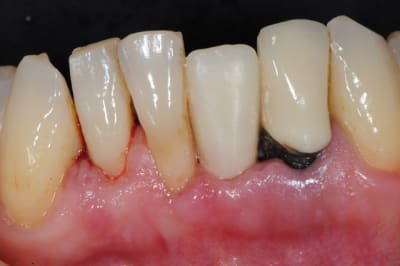

et ici ?? vous feriez quoi ?

32 et 42 pas mobiles

malheureusement, l'espace est réduit pour mettre deux implants.

comment avez vous déjà géré ce type de cas ??

le haut est déjà traité...

Img 0064 fykvs7 - Eugenol

Img 0066 bpmgnj - Eugenol

R2 bcqfqu - Eugenol

Img 0226 iaoqtw - Eugenol

003 penrd2 - Eugenol